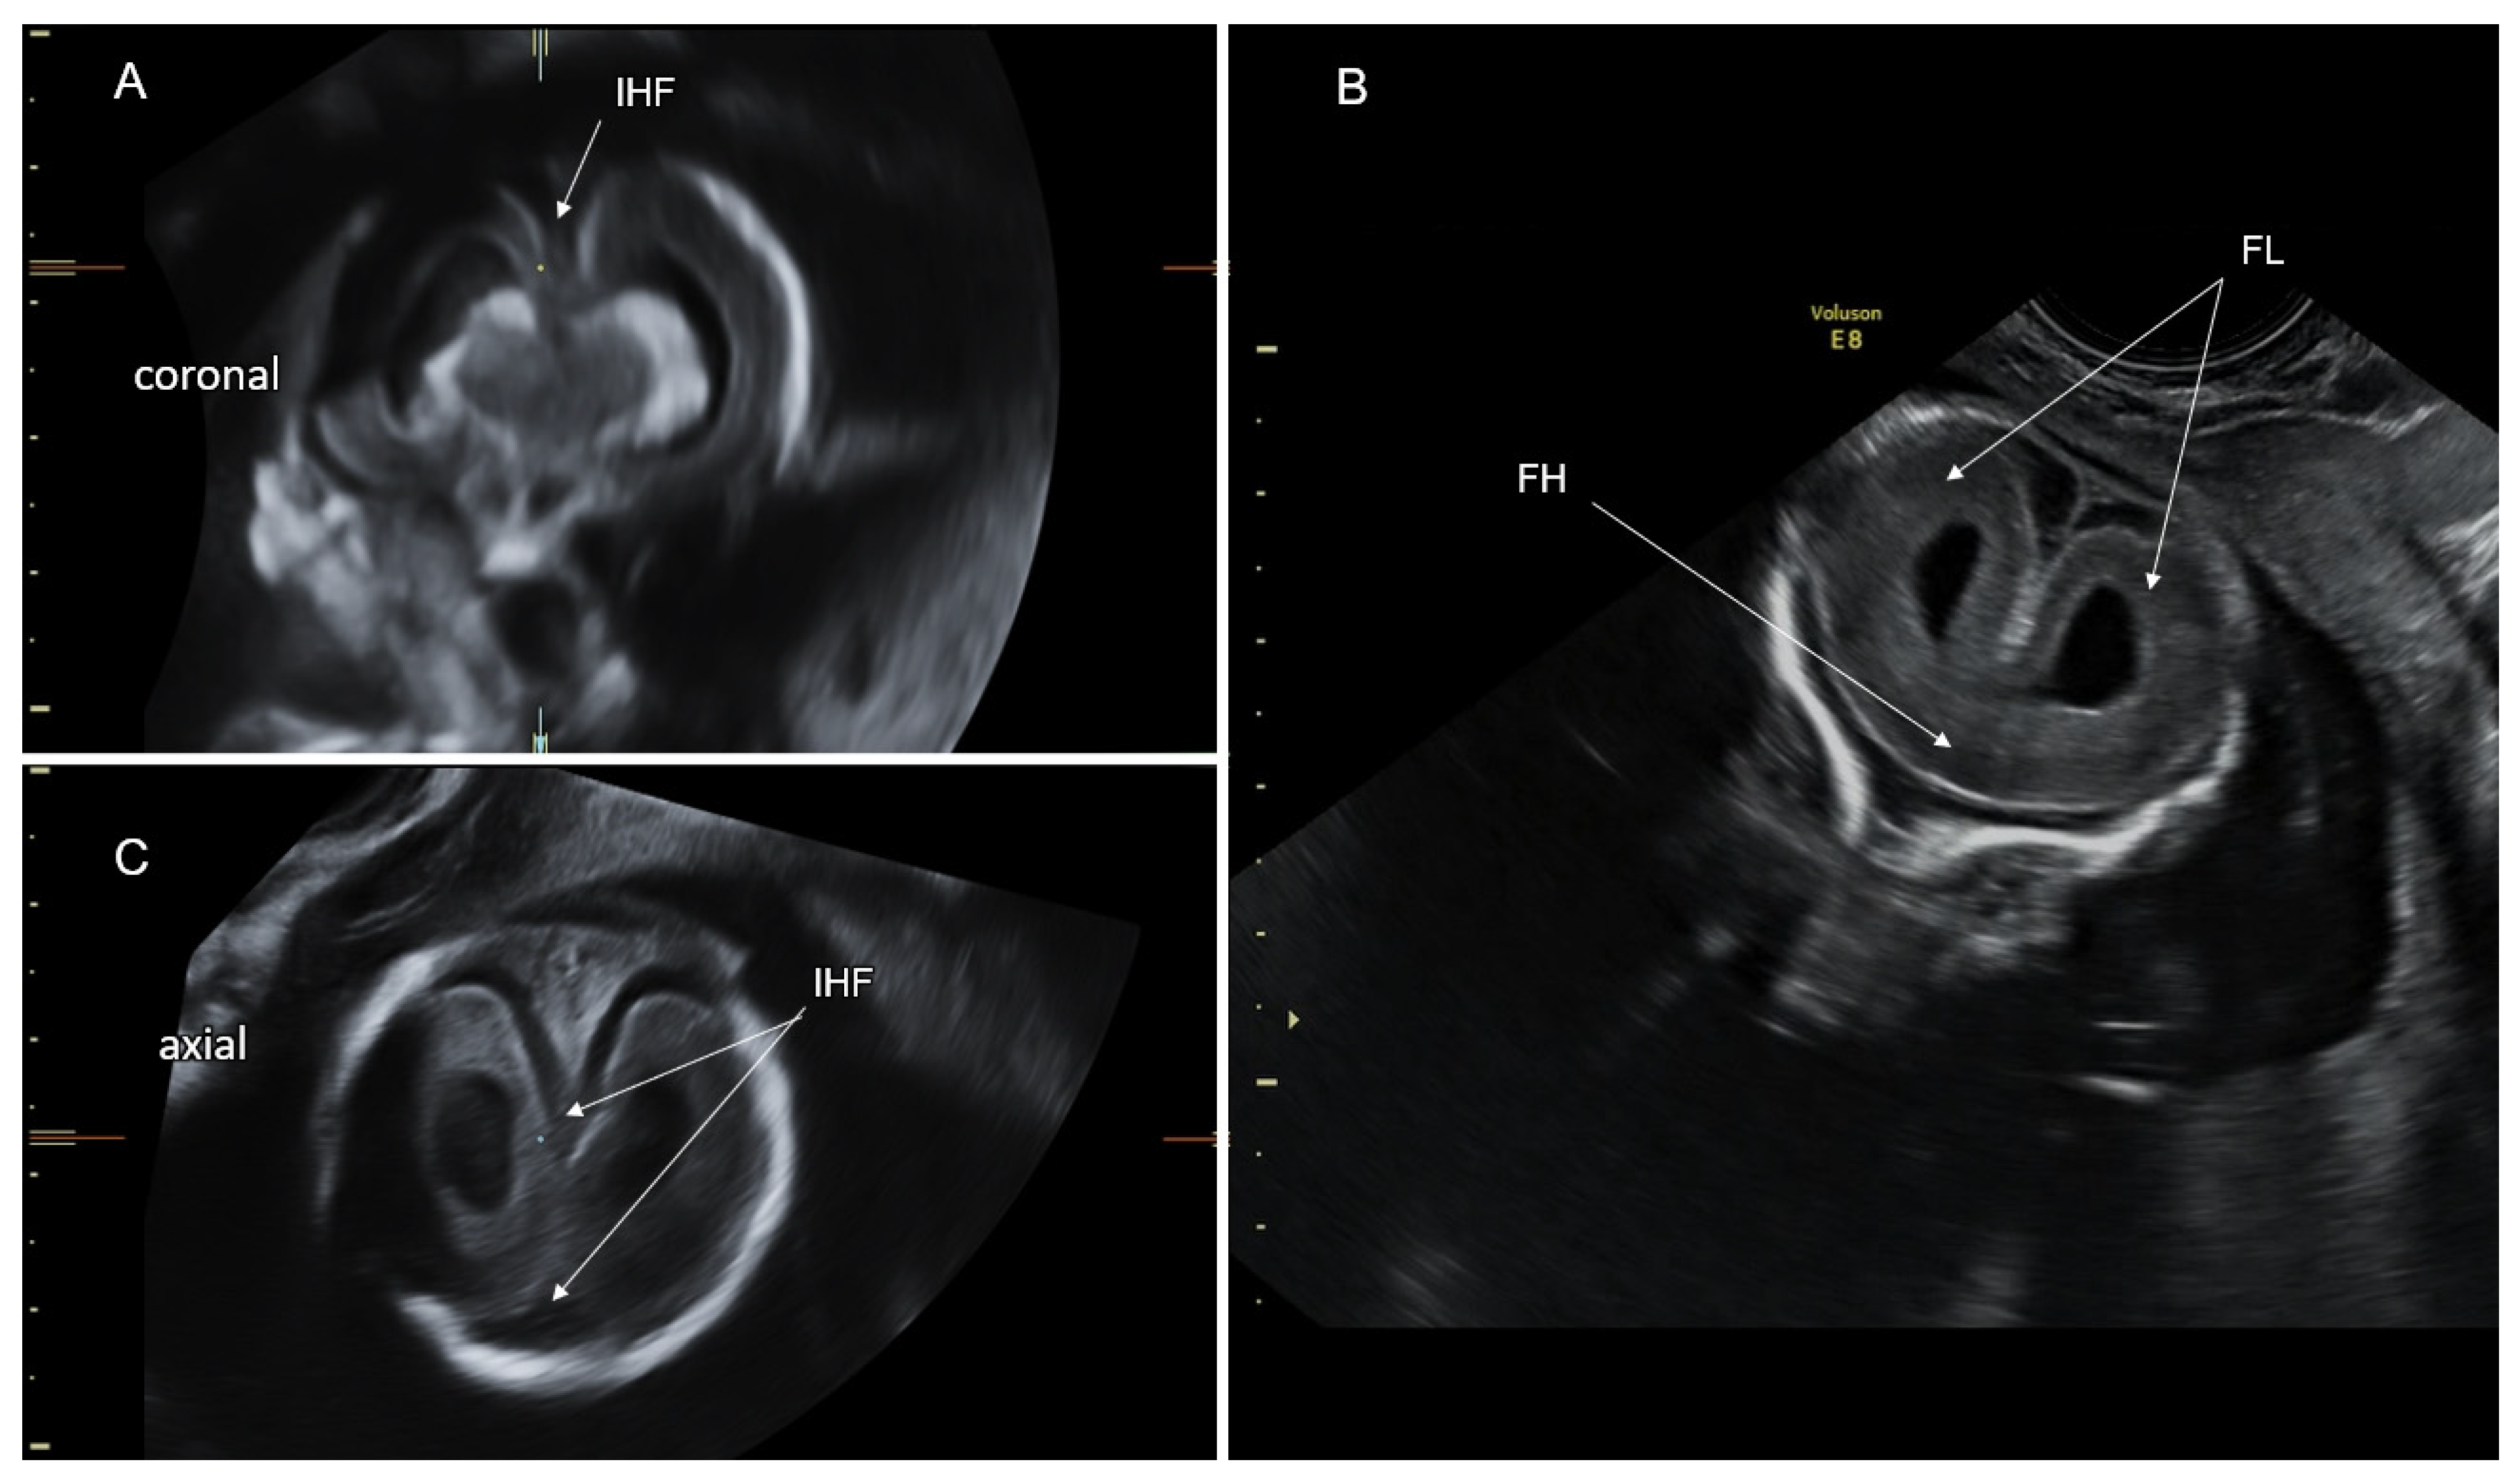

5. Disorders of the Corpus Callosum (DCC)